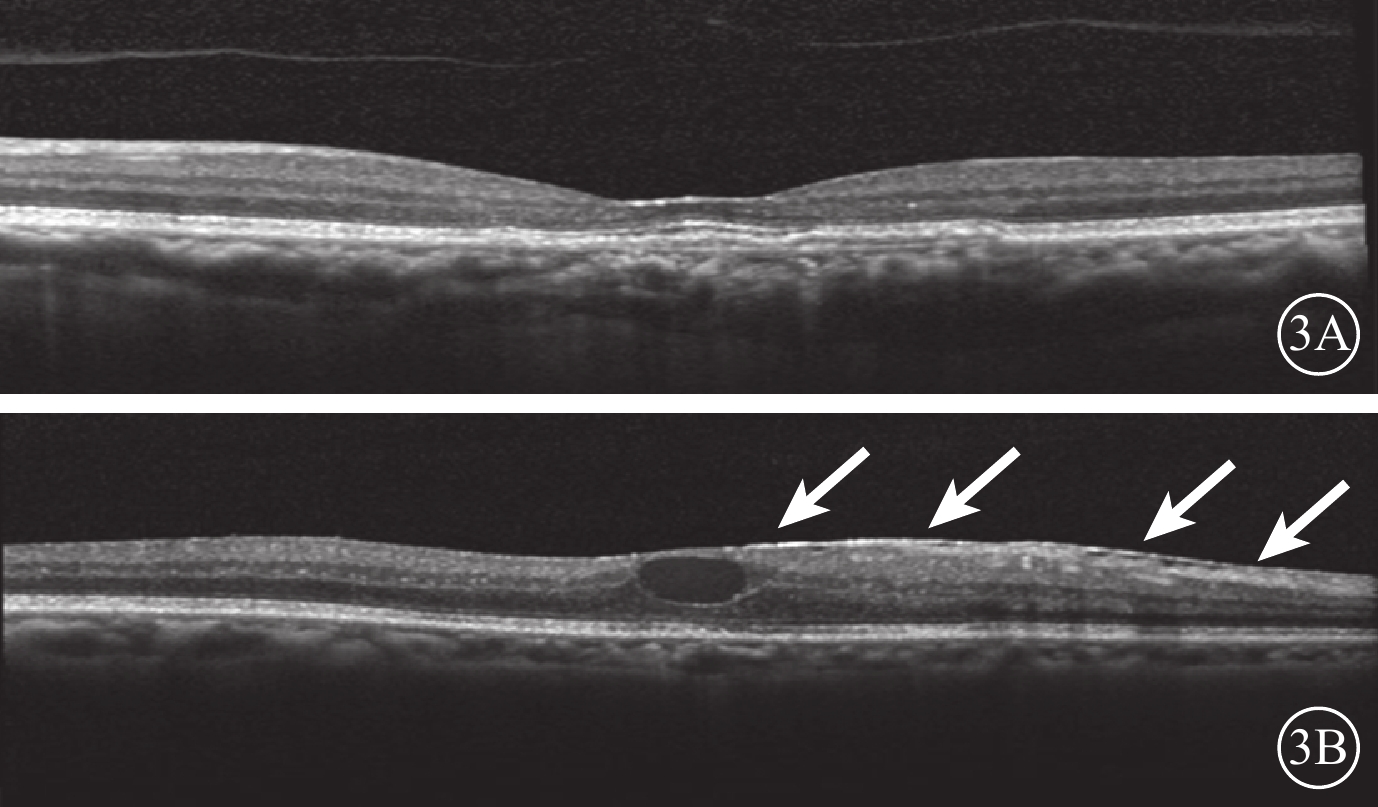

圖1

VMI異常的研究眼OCT像。1A. 黃斑中心凹區域局灶型VMA(白箭);1B. MEM(白箭)

圖1

VMI異常的研究眼OCT像。1A. 黃斑中心凹區域局灶型VMA(白箭);1B. MEM(白箭)

所有患者均采用3+PRN的方式接受玻璃體腔注射抗VEGF藥物治療。治療前采用OCT觀察患者雙眼的VMI情況。以中心凹為中心,掃描黃斑區,使用高速模式。(1)體積掃描:ART疊加次數9次,97線掃描線,20°×20°;(2)十字掃描:ART疊加次數36次,2線掃描線,20°×20°。將存在玻璃體黃斑粘連(VMA)、黃斑前膜(MEM)、完全性玻璃體后脫離(C-PVD)定義為VMI異常。以玻璃體粘附在中心凹中心3 mm直徑內,但部分玻璃體視網膜分離為VMA;并根據OCT圖像上玻璃體與黃斑部粘附的直徑大小將VMA分為局灶型(≤1500 μm)和廣泛型(>1500 μm)[17]。以鄰近或貼覆在黃斑前、較玻璃體后界膜厚且反射性強的組織為MEM[18]。以玻璃體后界膜高起,與視網膜黃斑無粘附為C-PVD[19-21]。34只研究眼中,存在VMI異常(圖1)12只眼。其中,廣泛型VMA 8只眼,局灶型VMA 3只眼,MEM 1只眼;合并存在局灶型VMA、MEM 1只眼。34只對照眼中,存在VMI異常(圖2)12只眼。其中,廣泛型VMA 7只眼,局灶型VMA 2只眼,C-PVD 2只眼,MEM 1只眼。治療后隨訪觀察12~26個月,平均隨訪時間16.4個月。隨訪期間每月用隨訪模式進行雙眼OCT檢查。對比分析患者雙眼治療前后VMI的變化情況。

圖1

VMI異常的研究眼OCT像。1A. 黃斑中心凹區域局灶型VMA(白箭);1B. MEM(白箭)

圖1

VMI異常的研究眼OCT像。1A. 黃斑中心凹區域局灶型VMA(白箭);1B. MEM(白箭)